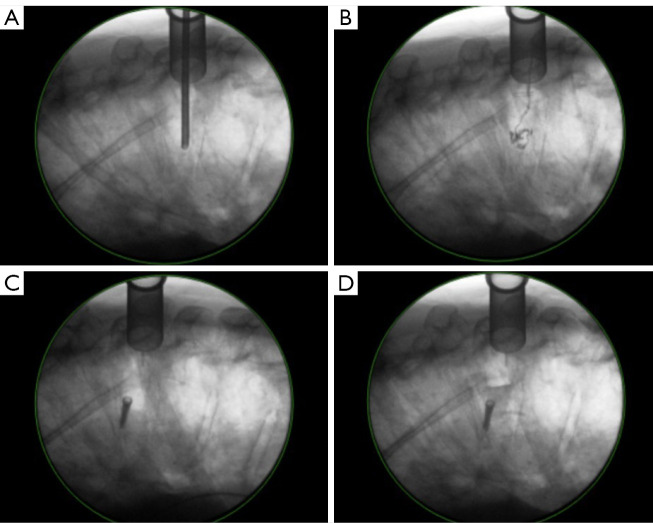

Abstract Image